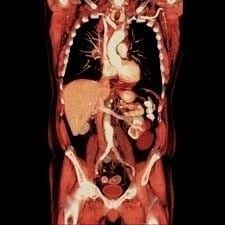

TAC OSTEOARTICOLARE

Permette di ottenere immagini dettagliate e in 3D delle strutture ossee e delle articolazioni, molto più precise di una semplice radiografia.

- TAC Rachide Cervicale

- TAC Rachide Dorsale

- TAC Rachide Lombo-Sacrale

- TAC Sacrococcigea

- TAC Spalla e Gomito/Arto Superiore

- TAC Polso e Mano

- TAC Bacino e Anca

- TAC Femore, Ginocchio e Gamba

- TAC Caviglia e Piede